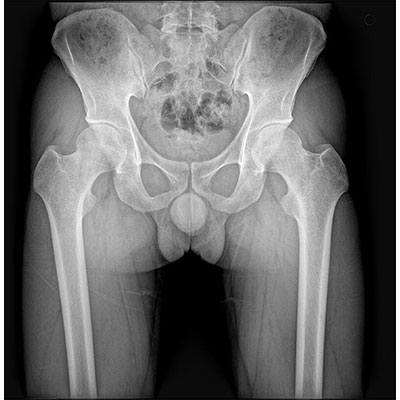

以微知形 為愛負責 微劑量 極速曝光 PLX8500E/F

● 短曝光、高熱容,拍片數量多、效率高。

● 輕松應對大型體檢中心高強度的拍片要求。

● 采用自主研發的技術,在保證優質圖像的前提下,大大降低X射線劑量,用心呵護醫護工作者及患者的健康。

● 短曝光時間,便于老年人、兒童、殘疾人進行臨床拍攝。避免這類群體因不能有效控制身體運動等因素造成的運動偽影,提高攝片質量及效率。